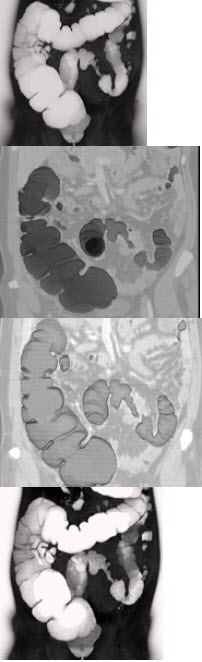

女,56岁,腹胀、腹痛、左下腹包块三月余,无肛门排气,影像检查如图,最可能的诊断是( )

A:乙状结肠Crohn病

B:乙状结肠结核

C:乙状结肠腺癌

D:乙状结肠淋巴瘤

E:乙状结肠息肉